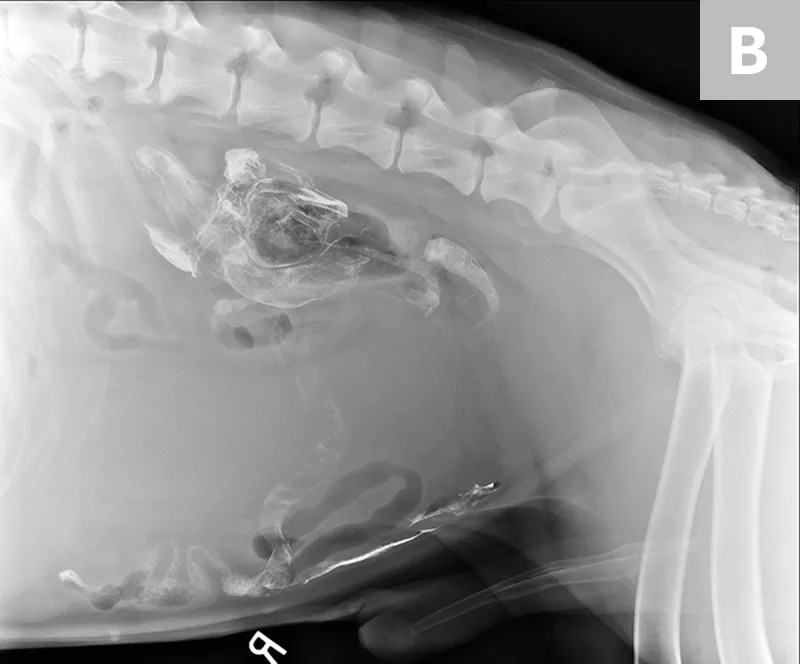

FIGURE 5

Splenic torsion appears as a large soft-tissue opacity that displaces the GI tract caudally and peripherally (A). The splenic head is obscured caudal to the left margin of the stomach (B). The metallic opacity seen in the stomach and intestines is caused by recent barium administration.